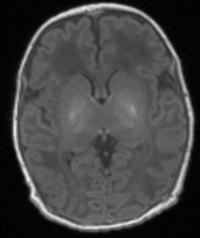

image: Scan one shows the brain of a healthy baby, while scan two shows that of a baby with brain damage. Compared to scan one, scan two shows abnormal brightness in the deep nuclei (in the centre of the brain), which indicates damage. view more

Credit: Imperial College London

Any child suspected of having some type of damage is given an MRI scan shortly after birth. This allows doctors to look at black and white pictures of the brain see if any areas of the brain look lighter than others, as this may suggest damage. Doctors then use this information to give parents an estimation of the extent of the damage, and the possible long-term disabilities their child may face.